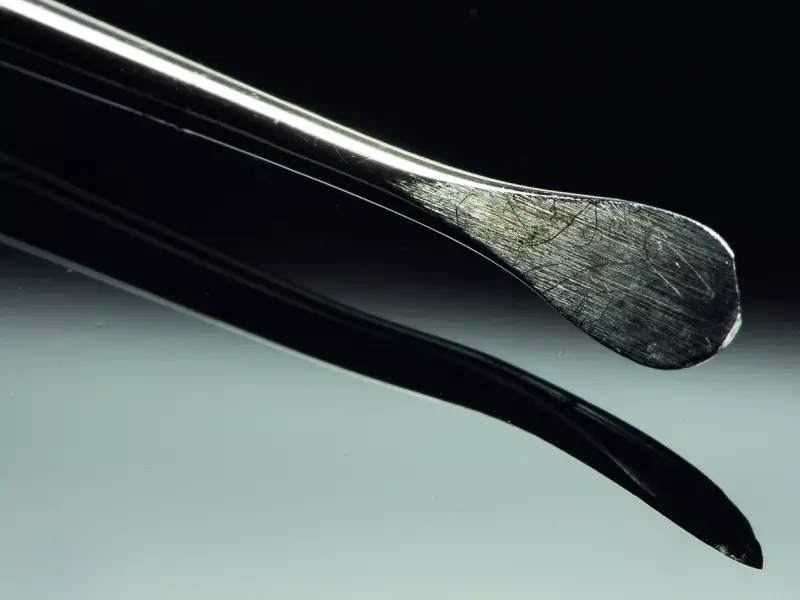

W dniu zabiegu ząb skruszono tak, aby uzyskać drobiny wielkości 800–1000 µm, które są optymalne dla procesu regeneracji kości. Po rozdrobnieniu otrzymano 1,5 cm³ materiału kostnego.